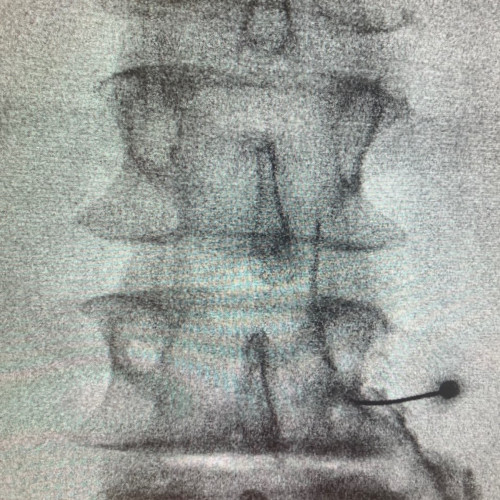

Röntgen-gezielte Infiltrationsbehandlung – Für eine Röntgen-gezielte Infiltrationsbehandlung ist ein stationärer Aufenthalt von einem Tag notwendig und wird von mir im Franziskusspital Margareten durchgeführt. Röntgengezielt sind auch Behandlungen mit Thermokoagulation und gepulster Radiofrequenz möglich.

CT-gezielte Infiltrationsbehandlung – Es kann die Nadel millimetergenau an die betroffene Region gebracht werden. Die Strahlenbelastung ist in etwa gleich der röntgengezielten Infiltration mit dem Vorteil der besseren Darstellung der Strukturen. Die CT-gezielte Infiltration wird von mir im Röntgeninstitut „Bellaria Diagnose“ im ersten Wiener Bezirk ambulant durchgeführt.